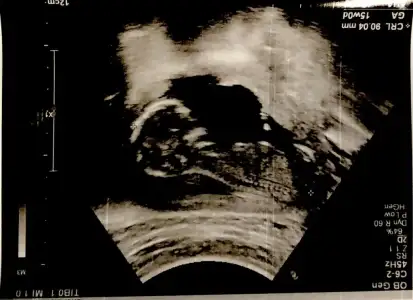

Eki Görüntüle 473829 bu bir erkek bebek genital nub cikintisi gayet yukarda

Eki Görüntüle 473831 simdi burada cikintilara bakin eger bel popo cizgisine paralel ise kiz

yok 30 derecelik bir aciyla yukari bakiyorsa erkek